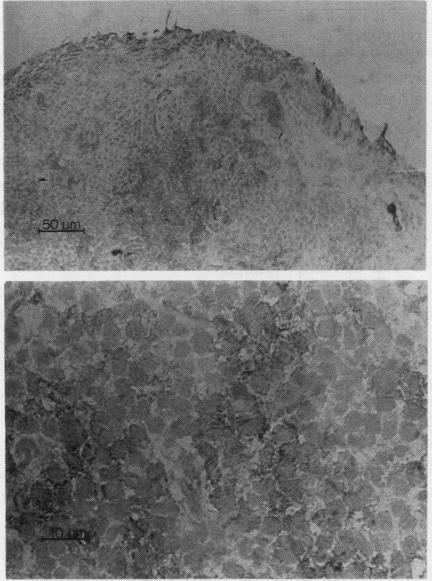

Synovial needle biopsy specimens from the knee joints of seven patients with rheumatoid arthritis (RA) were examined immunohistochemically before and after six months' treatment with either gold or penicillamine (disease modifying drugs, DMDs). There were significant reductions in the numbers of infiltrating T lymphocytes and a disproportionate fall in the numbers of lymphocytes of the helper/inducer subset when compared with those of the suppressor/cytotoxic subset. This resulted in a fall in the ratio of helper/inducer to suppressor/cytotoxic cells. The immunohistological changes correlated with improvements in erythrocyte sedimentation rate (ESR), serum immunoglobulins, visual analogue pain assessment, grip strength, and Ritchie articular index. A second group of nine patients with RA, already well established on DMD therapy, did not show similar changes after the six month period. The HLA class II antigens DR, DQ, and DP were widely expressed on lymphocytes, macrophages, and synovial lining cells of a group of patients with RA who had never received disease modifying drug therapy. After treatment there was a significant reduction in the expression of HLA-DP and DQ antigens.

对7例类风湿性关节炎(RA)患者膝关节的滑膜针吸活检标本在接受金制剂或青霉胺(病情缓解药物,DMDs)治疗6个月前后进行免疫组织化学检查。与抑制/细胞毒性亚群的淋巴细胞数量相比,浸润性T淋巴细胞数量显著减少,辅助/诱导亚群的淋巴细胞数量下降不成比例。这导致辅助/诱导细胞与抑制/细胞毒性细胞的比例下降。免疫组织学变化与红细胞沉降率(ESR)、血清免疫球蛋白、视觉模拟疼痛评估、握力和里奇关节指数的改善相关。另一组9例已接受DMD治疗且病情稳定的RA患者在6个月后未出现类似变化。一组从未接受过病情缓解药物治疗的RA患者的淋巴细胞、巨噬细胞和滑膜衬里细胞广泛表达HLA - II类抗原DR、DQ和DP。治疗后,HLA - DP和DQ抗原的表达显著降低。